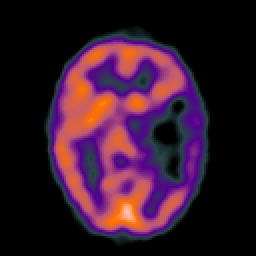

Metastatic bronchogenic carcinoma, overlay -- Slice #9

[Home][Help][Clinical] Slice 9